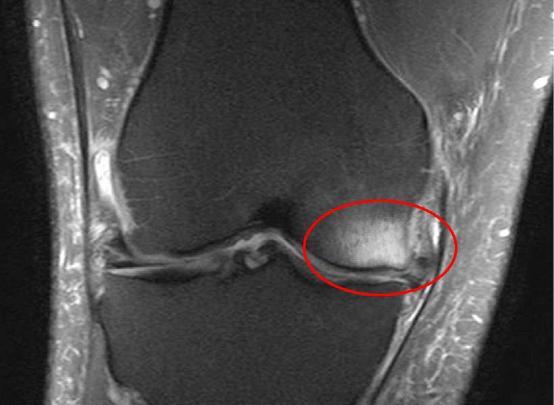

图片

1、骨挫伤是一种什么样的疾病

骨挫伤,又称为骨髓水肿(bone marrow edema,BME)在临床医生没有充分认识前,常被误诊和漏诊,随着核磁共振成像(MRI)技术的应用普及,诊断准确率得到了有效提高,该病曾经出现过多种名称描述,比如:特发性骨质疏松、痛性营养不良、暂时性骨髓水肿、原发性骨髓水肿、骨髓水肿综合征等。

骨髓水肿的病理过程主要表现为:病变骨组织灌注过度,导致液体外渗,引起骨基质水肿、纤维组织增生及炎性细胞浸润。此外,还表现为骨髓脂肪坏死,骨质吸收导致呈现骨质疏松样改变,骨髓组织呈水肿样变化,常伴有血管增生。骨髓水肿可以理解为微骨折。

4、怎么判断膝关节疼痛是由于骨挫伤造成的?

如果你的膝痛持续存在,并且并无好转,跑步还使得膝痛不断加重,那么最正确的处理方式就是到医院检查,建议找运动医学科或者运动损伤专科是最佳选择,如果没有运动医学科,也可以挂骨科或者康复科的号。

对于医生来说,往往也无法判断你的膝痛是不是骨髓水肿造成的,但医生会通过询问病情并通过检查进行准确诊断。对于骨挫伤来说,最有效精准的诊断手段就是核磁共振检查。核磁共振图像显示骨髓异常十分敏感,可以明确骨髓水肿的范围和严重程度。